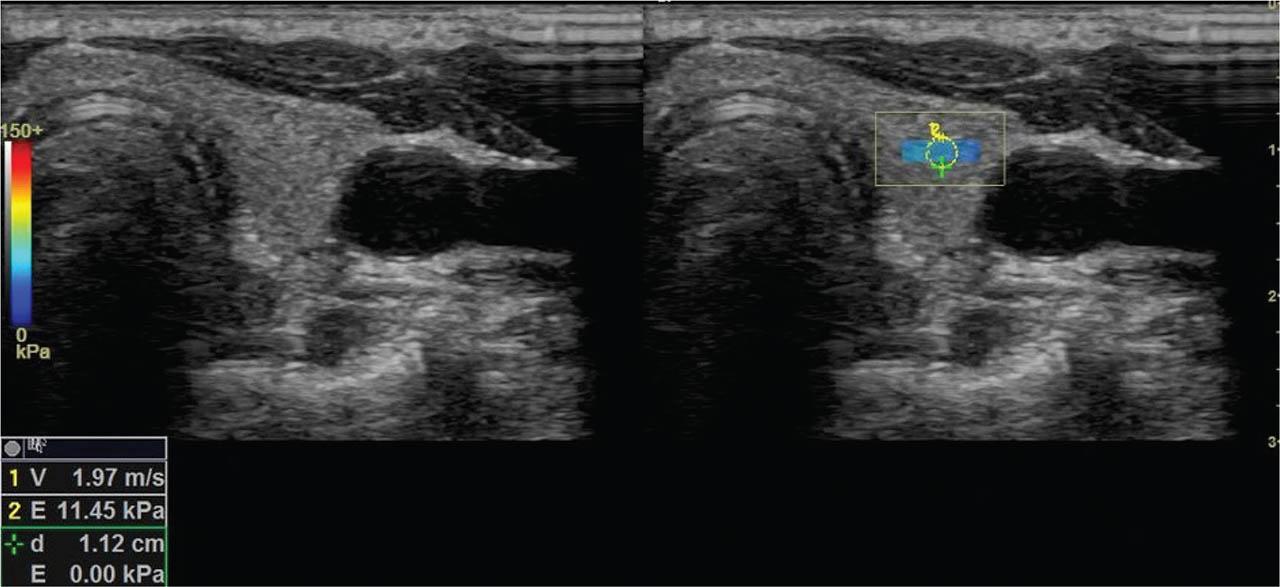

Figure 2